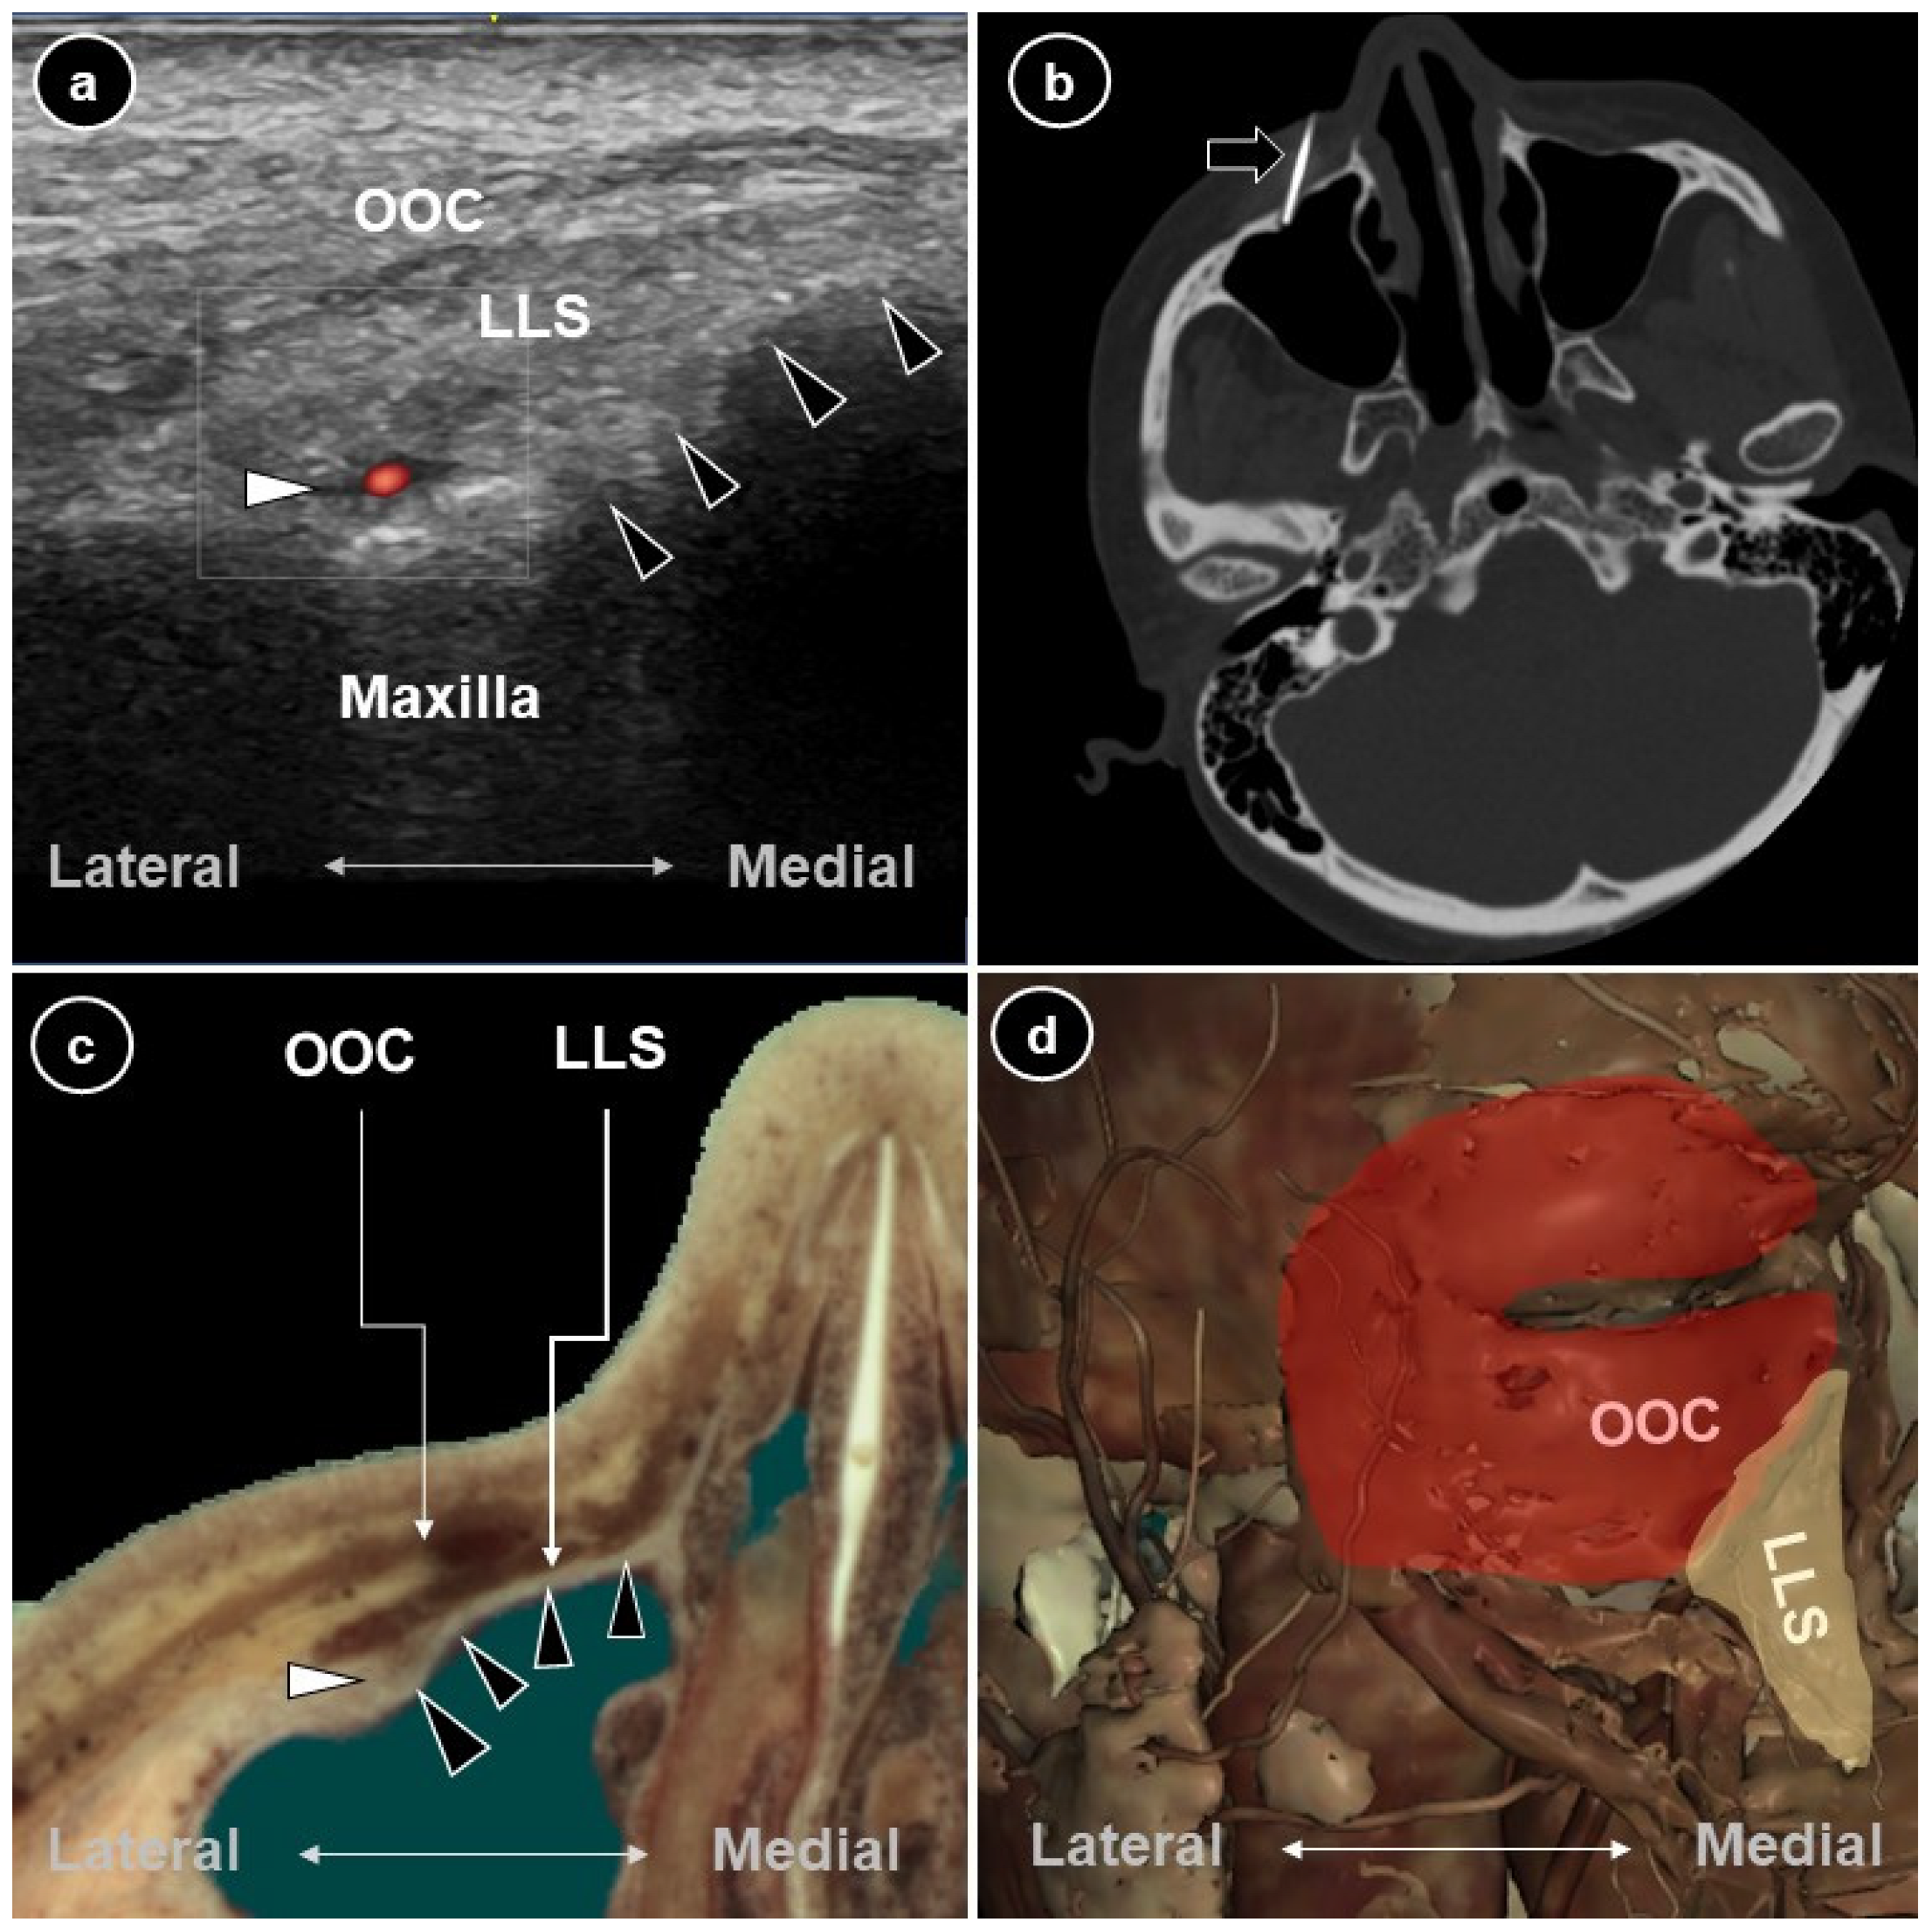

Ultrasound- and CT-Guided Medial-to-Lateral Radiofrequency Ablation of the Infraorbital Nerve for Persistent Idiopathic Dentoalveolar Pain: A Trajectory-Based Approach